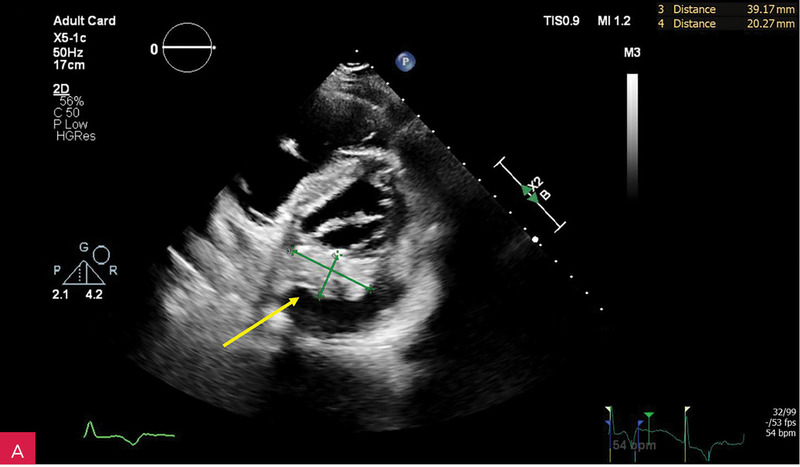

Rycina 2A, B. Zmiana u podstawy tylnego płatka mitralnego, obejmująca jego nasadę, a także fragment mięśnia ściany dolno-bocznej lewej komory w projekcji przymostkowej w osi długiej LAX (A) oraz w projekcji zmodyfikowanej, w której lepiej uwidoczniono hiperechogeniczną uwapnioną otoczkę zmiany oraz powodowany przez nią cień akustyczny (B)